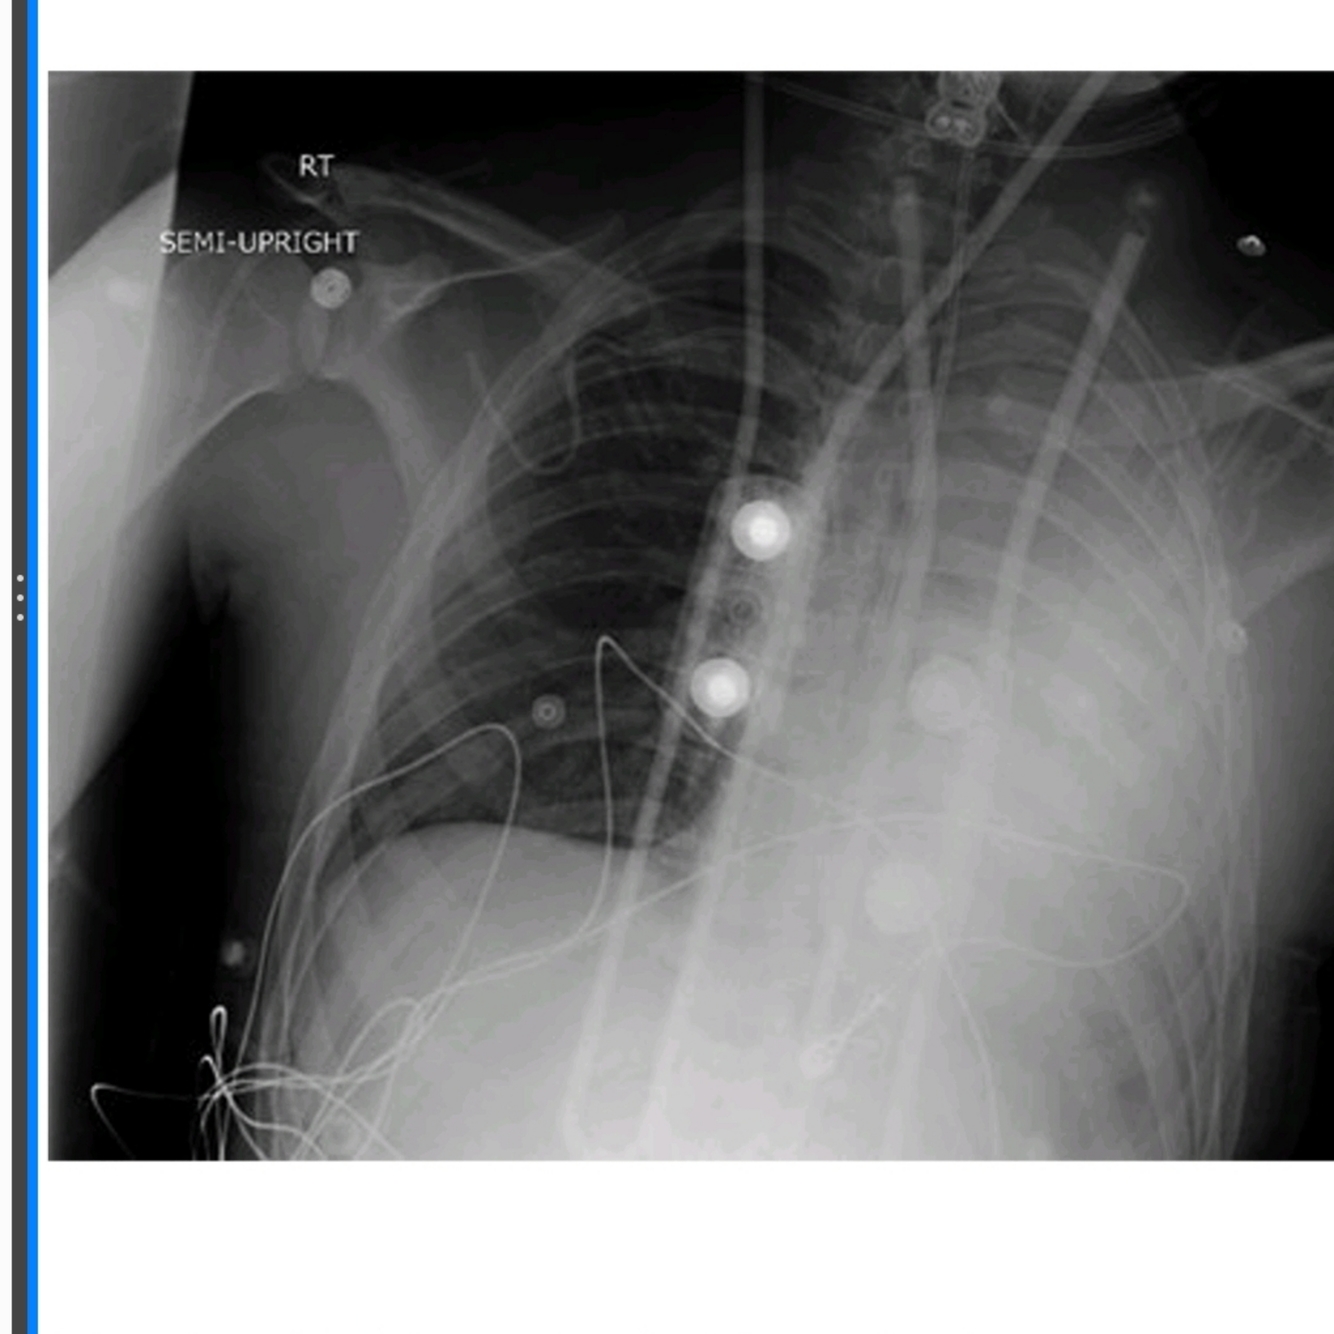

What do the images above show and what is the differential diagnosis based on the appearance seen in the images above?

○ The chest X-ray (Fig. 47.1) shows diffuse bilateral coalescent opacities, whereas the CT chest (Fig. 47.2) shows ground-glass opacification, reflecting an overall reduction in the air content of the affected lung. It is also possible to visualize bronchial dilatation within areas of ground-glass opacification.

Differential diagnosis include

(a) ARDS,

(b) congestive heart failure,

(c) pulmonary hemorrhage,

(d) pneumonia,(

e) transfusion-related acute lung injury, and

(f) non-cardiogenic pulmonary edema.